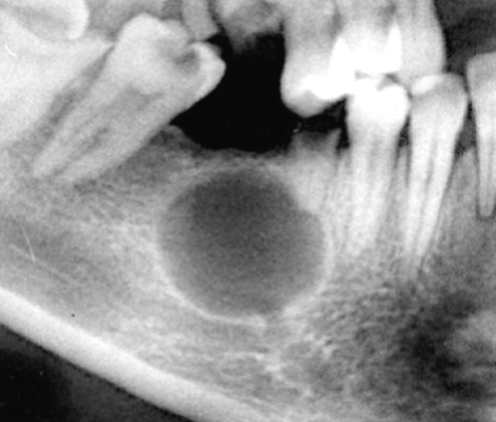

Describe this Radicular Cyst

Epicenter at apex (usually evidence of dental disease or trauma)

Well-defined, corticated

Lucent

Circular

Resorption, Displacement, Expansion (effect on adjacent structures)